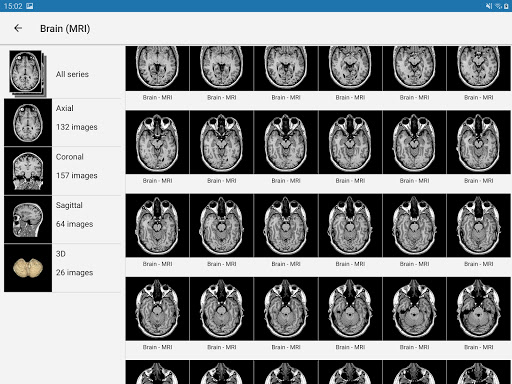

e-Anatomy tiene más de 26 000 imágenes que contienen series de imágenes en vistas axiales, coronales y sagitales, así como radiografías, angiografías, imágenes de disección, gráficos anatómicos e ilustraciones. Todas las imágenes médicas fueron etiquetadas cuidadosamente, más de 967 000 etiquetas disponibles en 12 idiomas, incluida la Terminologia Anatomica latina.

- Desplácese por los conjuntos de imágenes arrastrando el dedo

- Acerque y aleje el zoom